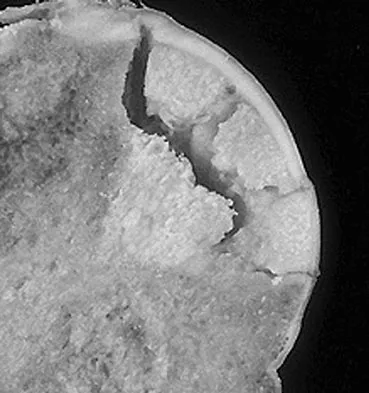

A 30-year-old patient has had severe left hip pain and difficulty ambulating, necessitating the use of a cane, for the past 6 months. A photomicrograph of the femoral head sectioned at the time of surgery is shown in Figure 31. What is the most likely diagnosis?

General Orthopedics 2026 Practice Questions: Set 5 (Solved) - Figure 1

Detailed Explanation

The photomicrograph demonstrates a wedge-shaped infarct with femoral head collapse; therefore, the diagnosis is osteonecrosis of the femoral head. Perthes disease and osteoarthritis do not involve a wedge-shaped defect. Tuberculosis of the hip joint results in greater destruction of the articular cartilage. Basset LW, Mirra JM, Cracchiolo A III: Ischemic necrosis of the femoral head: Correlation between magnetic resonance imaging and histologic sections. Clin Orthop 1987;223:181-187.